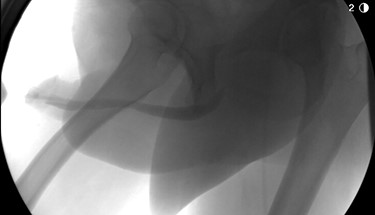

The patient underwent further evaluation with imaging including renal ultrasound, which was normal. Flexible cystourethroscopy demonstrated a circumferential urethral mass concerning for urothelial carcinoma (Fig. 1), which was biopsied with histopathology negative for urothelial carcinoma but positive for amyloid protein deposition. Examination of the external genitalia was unremarkable and there was no palpable induration along the ventral penile shaft. Systemic workup for additional manifestations of amyloidosis was negative. Imaging with retrograde urethrography (RUG) demonstrated an ~2 cm segment of urethral stenosis in the penile urethra (Fig. 2).

Endoscopic visualization of circumferential amyloid protein deposition causing urethral luminal narrowing.